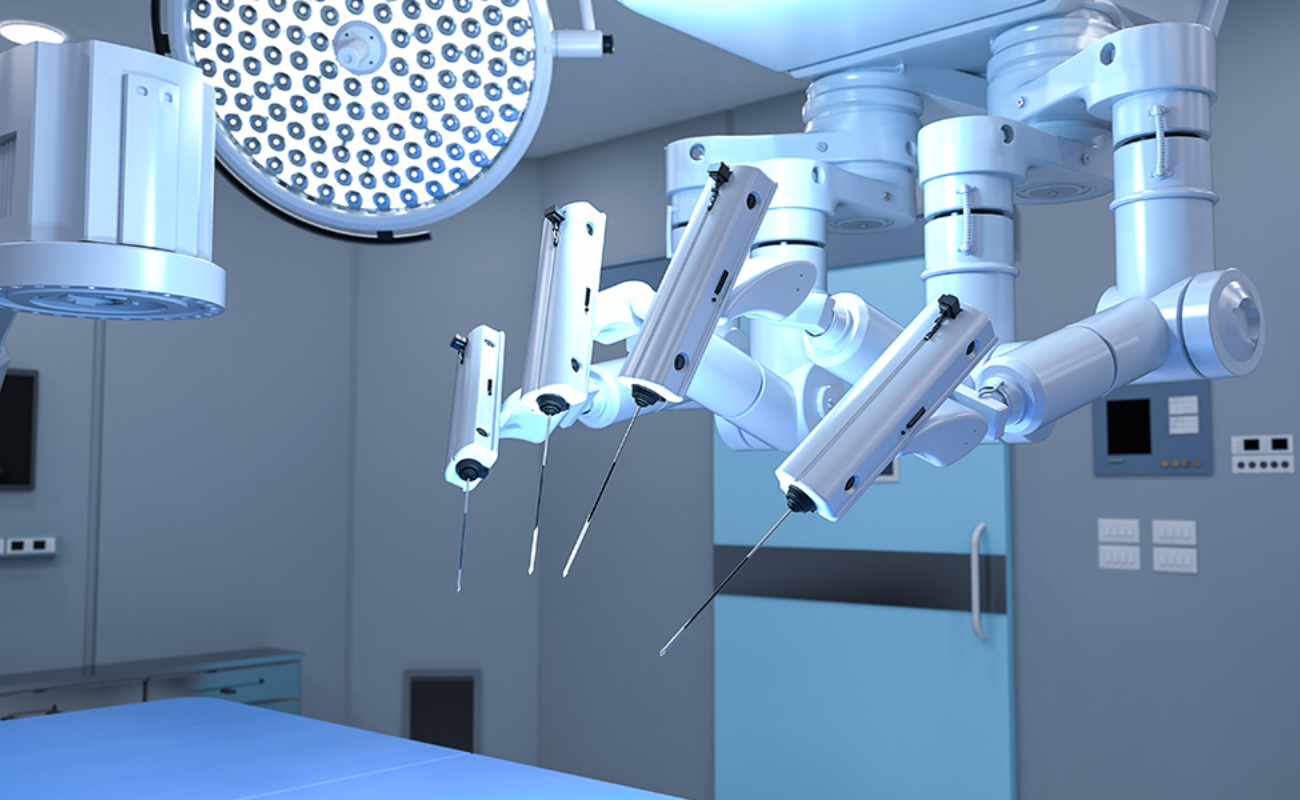

With state-of-the-art robotic joint replacement surgery offering greater accuracy, smaller incisions, and faster recovery times.

Advanced Facilities

Dr. Patel's state-of-the-art facility is equipped with the latest technology and equipment, ensuring that patients receive the most advanced care available

The Benefits of Robotic Knee Replacement Surgery

In recent years, medical technology advancements have brought about a revolution in the field of orthopedic surgery, particularly in the realm of knee replacements.

The Impact of Robotics on Knee Replacement: Revolutionizing Orthopedic Surgery

In recent years, orthopedic surgery has undergone a revolutionary transformation through the integration of robotics in knee replacement procedures.

Robotic Surgery: The Future of Healthcare in Chennai

Robotic surgery is revolutionizing healthcare, particularly in Chennai, where advanced medical techniques are becoming increasingly accessible

Robotic Surgery in Chennai: A Guide for Patients and Caregivers

Robotic surgery is transforming modern healthcare, offering precision, minimally invasive techniques, and faster recovery for patients. As one of the most significant advancements in surgical technology,

Modern Technology Makes Robotic Surgery Safer Than Ever

In the world of surgery, one technology that has made waves since its introduction is robotic surgery. It has swiftly moved from novelty to necessity in the medical world. Robotic surgery has changed every surgeon’s